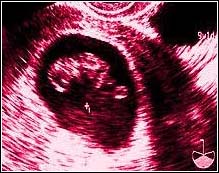

Week Four. Three and a half weeks later, we get our first peek.

Our child is now 2.8 millimeters in length, smaller than a grain of rice. Yet we can clearly see a heart beating!

The due date is set at June 4, 1999.